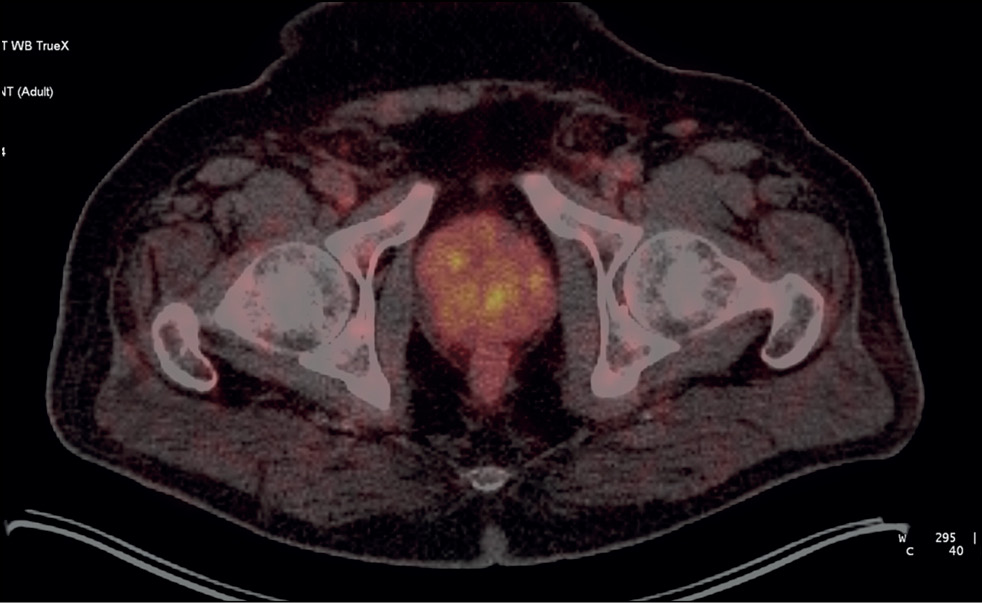

Patient M., 6 years old, had an increased PSA level of 6.8 ng/mL and underwent a multifocal prostate biopsy at a local clinic. The diagnosis was confirmed morphologically as adenocarcinoma, Gleason 6 (3 + 3), based on data from the transitory zone of the right prostate lobe. Adenocarcinoma elements were not found in other prostate biopsy specimens. Considering MRI evidence of changes in the same zone, implantation with 30 125I sources with a 32-cm3 volume was proposed.

SPECT/CT with 99mTc-HYNIC-PSMA revealed diffuse focal RP accumulation under the base of the bladder. PET/CT with 68Ga-PSMA-11 was additionally performed to more accurately visualize prostate lesions. PET/CT revealed multiple sites of RP accumulation in the prostate gland, indicating that the tumor was multifocal (Figure 8). Implantation planning was adjusted to include the total volume of the prostate gland (78 cm3) using 90 125I microsources (instead of preliminary 30 microsources).

Fig. 8. Patient M., 69 years old, PET/CT with 68Ga-PSMA-11: Sites of radiopharmaceutical accumulation in the prostate gland, multifocal tumor.

On February 25, 2022, implantation was performed for the total volume of the prostate gland. The initial prostate volume for brachytherapy was 32 cm3. PET/CT revealed a volume of 72 cm3 for implantation. The PSA level decreased to 0.31 ng/mL within a year after brachytherapy.